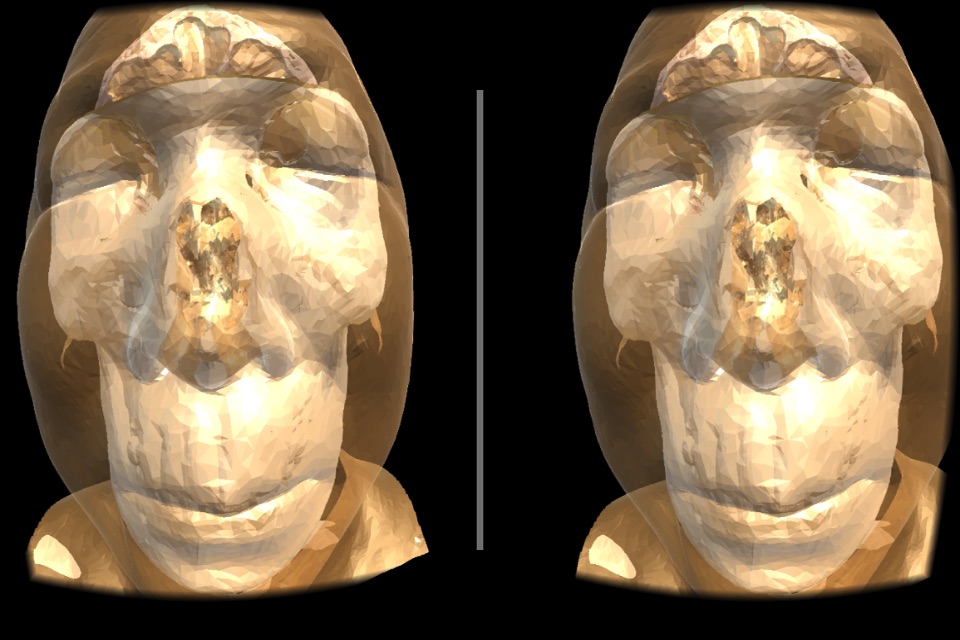

VR Body Guideは、まるで目の前にあるように、

人体の内部の様子をリアルに眺めて、

人体の不思議を楽しむことができる、医学教育用アプリです。

実際のCT画像から起こされた、本物の内臓のモデルを、間近に見ることができます

(これは似せて作られたモデルではありません!)。

・鑑賞するモデルは「頭部」と「胴体」の2種類です。

頭部は脳、頭蓋骨、皮膚のそれぞれの表示をON/OFFできるようになっています。